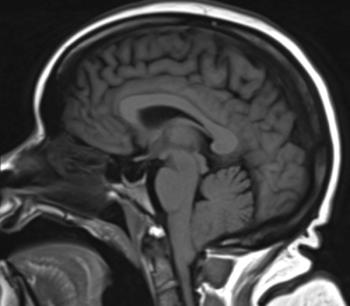

52-year-old female with vertigo, headache, tinnitus, eye twitching, and general instability while walking.